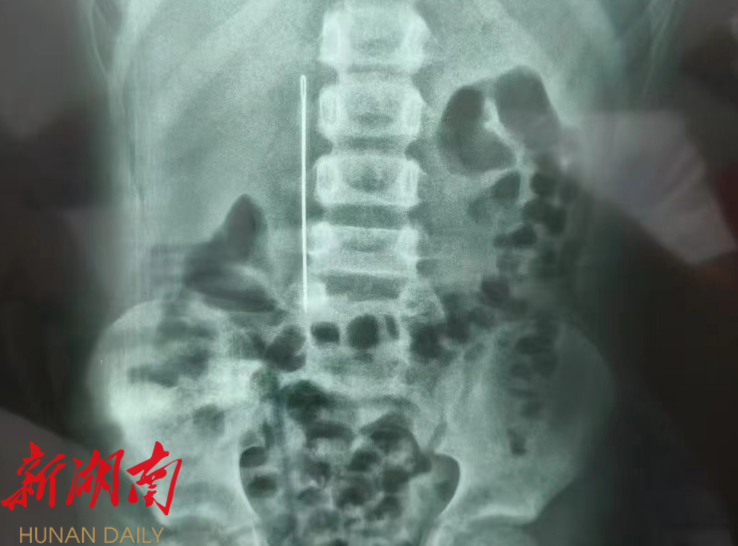

湖南日报·新湖南客户端7月14日讯(通讯员 代欢 邓燕芳)6月28日晚,永兴县人民医院上演了一场惊心动魄的生命救援。一名9岁男童因误吞9厘米长缝被针,出现腹痛症状紧急送医。经CT检查显示,这根缝被针已刺入男童胃壁,若不及时取出,随时可能引发大出血、胃肠穿孔,甚至伤及邻近器官或腹腔大血管,威胁生命安全。

手术过程中,需要操作胃镜进入男童胃部。面对胃内食物残渣干扰视野、缝被针深深嵌入胃壁等难题,科室医生凭借精湛的技术,成功用器械夹住缝被针。然而,取出异物的过程才是真正的“闯关”挑战。缝被针需依次通过贲门、紧邻心脏大血管的主动脉弓区域,以及狭窄弯曲的食管入口。

在通过前两关时,凭借丰富的临床经验,手术团队沉稳应对,顺利通过。但在最为险峻的第三关——食管入口处,意外发生,缝被针卡在会厌处,导致局部出现少量出血。关键时刻,科室主任带领团队冷静操作,通过反复调整吸引角度与力度,最终成功将整根9厘米长的缝被针安全取出。术后经检查,男童消化道未出现明显损伤,身体状况稳定。